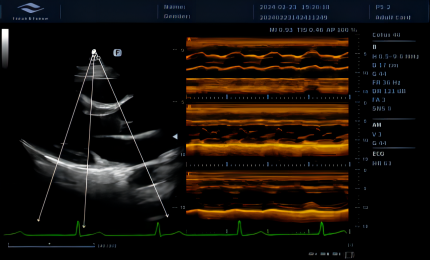

Umożliwia ustawienie kursora M-trybu pod dowolnym kątem na cyfrowych obrazach dwuwymiarowych. Trzy linie próbkowania pozwalają lekarzowi mierzyć jednocześnie trzy pozycje, a każda linia próbkowania może być obrócona o 360°.

Technologia krzywoliniowego M-Mode (CAM) umożliwia wyświetlanie wszystkich przestrzennych i czasowych relacji ruchów segmentów mięśnia sercowego podczas cyklu sercowego w sektorze skanowania. Zapewnia to nową metodę pomiaru do ilościowej analizy zaburzeń ruchów segmentów mięśnia sercowego podczas fazy skurczowej lub rozkurczowej.

Obrazowanie tkankowe metodą Dopplera (TDI) to solidne i powtarzalne narzędzie echokardiograficzne, które wykorzystuje efekt Dopplera do oceny charakterystyk ściany mięśniowej w całym cyklu sercowym, obejmując prędkość, przemieszczenie, deformację oraz timing zdarzeń. Pozwala na ilościową ocenę zarówno globalnej, jak i regionalnej funkcji oraz timing zdarzeń miokardialnych.